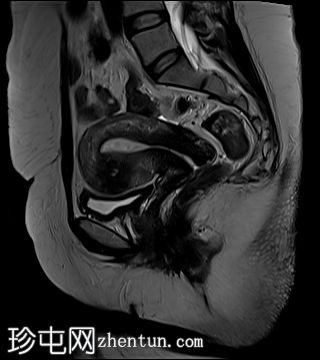

冠状位

T1加权像

子宫前壁交界区局灶性增厚,边界不清。形成直径约3厘米的局灶性肿块样病变,轻度压迫膀胱。肿块边界模糊不清,可见多个细小出血灶,在T1加权像和T2加权像上均呈高信号,提示局灶性子宫腺肌症。

子宫体前壁可见另一处病灶,位于上述病灶尾侧,边界清晰(有包膜)。该病灶在T1和T2加权像上均呈低信号,内部未见异常信号灶,周围可见少量明显血管通道,提示为小型子宫肌瘤。

左侧卵巢可见数个小囊肿,在T1加权像上呈高信号,在T2加权像上呈低信号(T2阴影),T1脂肪抑制序列未见信号下降,提示其为血液降解产物。最大的囊肿轴位大小约为3.1×1.7 cm,轻度压迫卵巢实质。

右侧卵巢可见黄体囊肿。未见实性肿块。

盆腔少量游离液体。

边界模糊不清是局灶性子宫腺肌症(无包膜)的特征。此外,病灶内存在多个微小的内部出血灶(异位腺体),且邻近增厚模糊的交界区,这些都是局灶性子宫腺肌症的诊断标准。

在上述病灶尾侧可见另一处具有不同影像学特征的病灶,该病灶边界清晰(有包膜),且信号均匀(无微小的内部出血灶),提示可能合并子宫肌瘤。